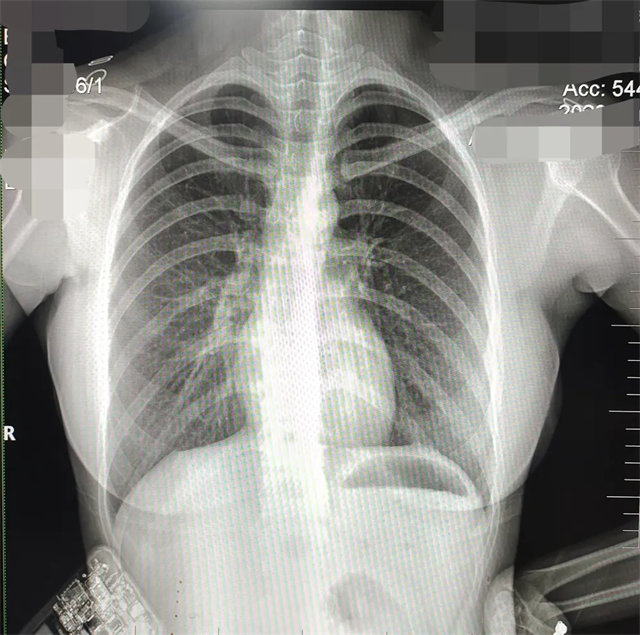

缺陷:肩胛骨未完全拉離肺野,吸氣不完全,存在金屬偽影遮擋,略有聳肩,且肺尖顯示不好,圖像顆粒感較強,管電流量不夠,信噪比偏低。

解決:去除金屬物品后,按標準體位,使患者雙肩旋前與前胸一并緊貼成像件,適當(dāng)調(diào)高mAs,然后深吸氣后屏氣曝光。